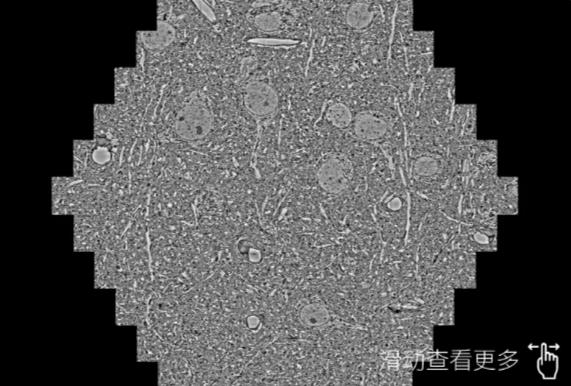

鼠脑切片。左图使用山东蔡司山东扫描电镜MultiSEM706对165μmx143pm面积区域成像,耗时仅需1.5秒。右图为鼠脑切片中30μm区域放大效果。样品由芝加哥大学B.Kasthuri提供。

使用蔡司高速山东扫描电镜MultiSEM对1mm²人脑皮层组织进行高分辨成像,并对其中的各种细胞结构进行三维重构分析。左图展示了2x3mm²组织平面中锥体神经元的三维重构效果。右图显示了局部体积神经元三维重构。图像由哈佛大学chtman实验室提供,渲染图由D. Berger 制作。